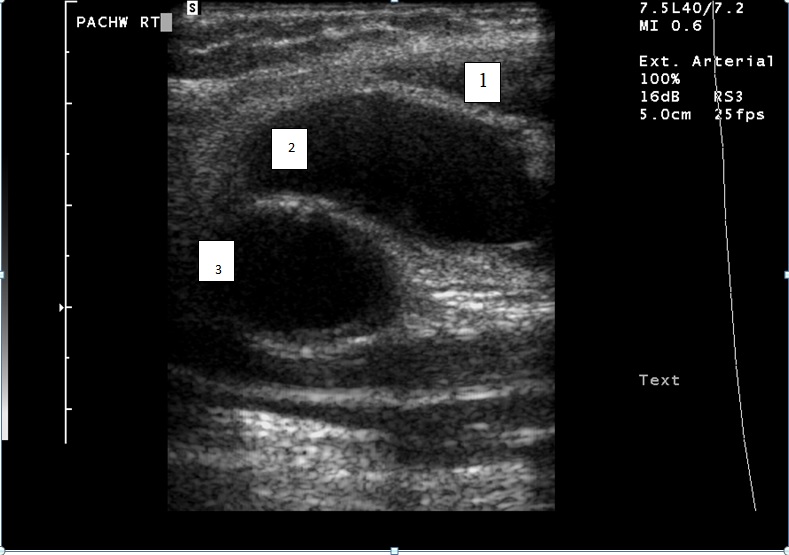

Na rycinie przedstawiono obraz uzyskany po poprzecznym przyłożeniu liniowej głowicy ultrasonograficznej w pachwinie lewej. Zaznaczone cyframi struktury odpowiadają: